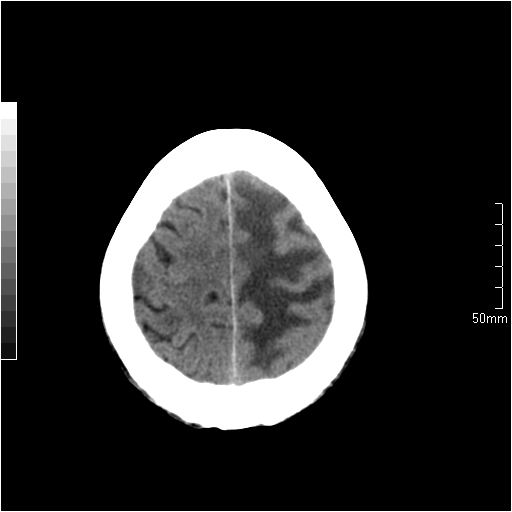

以下是引用天南地北在2007-6-25 12:39:00的发言:[br]有占位效应[br]支持术后复发

以下是引用zjzjr在2007-6-25 12:38:00的发言:[br]左侧复发,右侧转移。